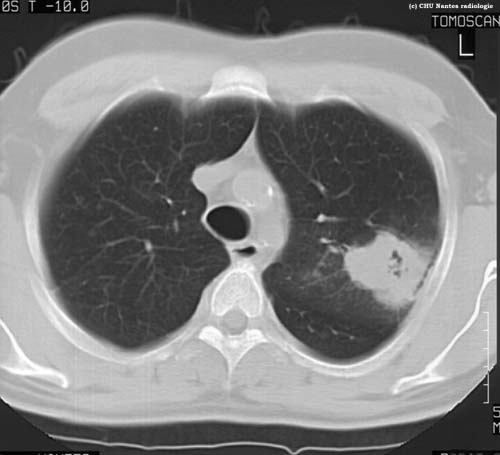

Lésions cavitaires : coupe

TDM